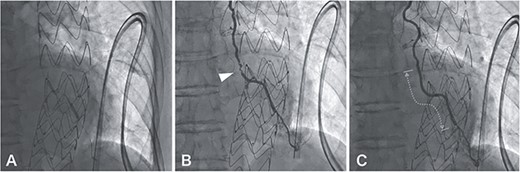

MIDCAB, harvesting of a pedicled LITA followed by an end-to-side anastomosis to the LAD with a sufficient intraoperative graft flow, was performed through left anterior mini-thoracotomy. Although the patient’s chest symptoms were vague and serum cardiac biomarkers were not elevated postoperatively, routine contrast-enhanced multi-slice CT (MSCT) on postoperative Day 3 suggested the middle of LITA graft occlusion (Fig. 1A). The following CAG also demonstrated thrombotic occlusion (Fig. 1B and C). Subsequently, we performed PCI for the lesion in the LITA graft. The lesion was crossed with a 0.014-inch guidewire (SION Blue, Asahi Intecc, Aichi, Japan); afterward, balloon dilation (Ryurei 2.0 × 20 mm, Terumo, Tokyo, Japan) was performed repeatedly. Three stents (Synergy 2.25 × 12 mm, 2.25 × 28 mm, 2.25 × 20 mm; Boston Scientific, USA) were overlappingly placed to cover the lesion, and a satisfactory angiographic result was observed (Fig. 2). The patient had an unremarkable hospital stay and remained symptom-free 2 years postoperatively.

A 0.014-inch guidewire (SION Blue, Asahi Intecc, Aichi, Japan) was inserted into the LITA graft under intravascular ultrasound (Altaview; Terumo, Tokyo, Japan) guidewire; the diameter of the lesion was about 2 mm, therefore balloon dilation (Ryurei 2.0 × 20 mm, Terumo, Tokyo, Japan) was performed first from distal to proximal (A); angiography showing hematoma formation in the lesion, which was not resolved by the administration of nitroglycerin (B, arrowhead); three stents (Synergy 2.25 × 12 mm, 2.25 × 28 mm, 2.25 × 20 mm, Boston Scientific, USA) were overlappingly placed to cover the lesion (C, dotted line), and there was a satisfactory angiographic result.